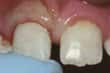

Сколотый передний зуб    Chipped front tooth

Chipped tooth —If there is no pain and the chip is small, it's up to you to decide if, when and how the tooth should be repaired. Depending on the size of the chip, it can be smoothed or cosmetically corrected. Other options include veneers, crowns and fillings. Ask your dentist to explain these options. If a filling or artificial tooth becomes chipped, it should be replaced.